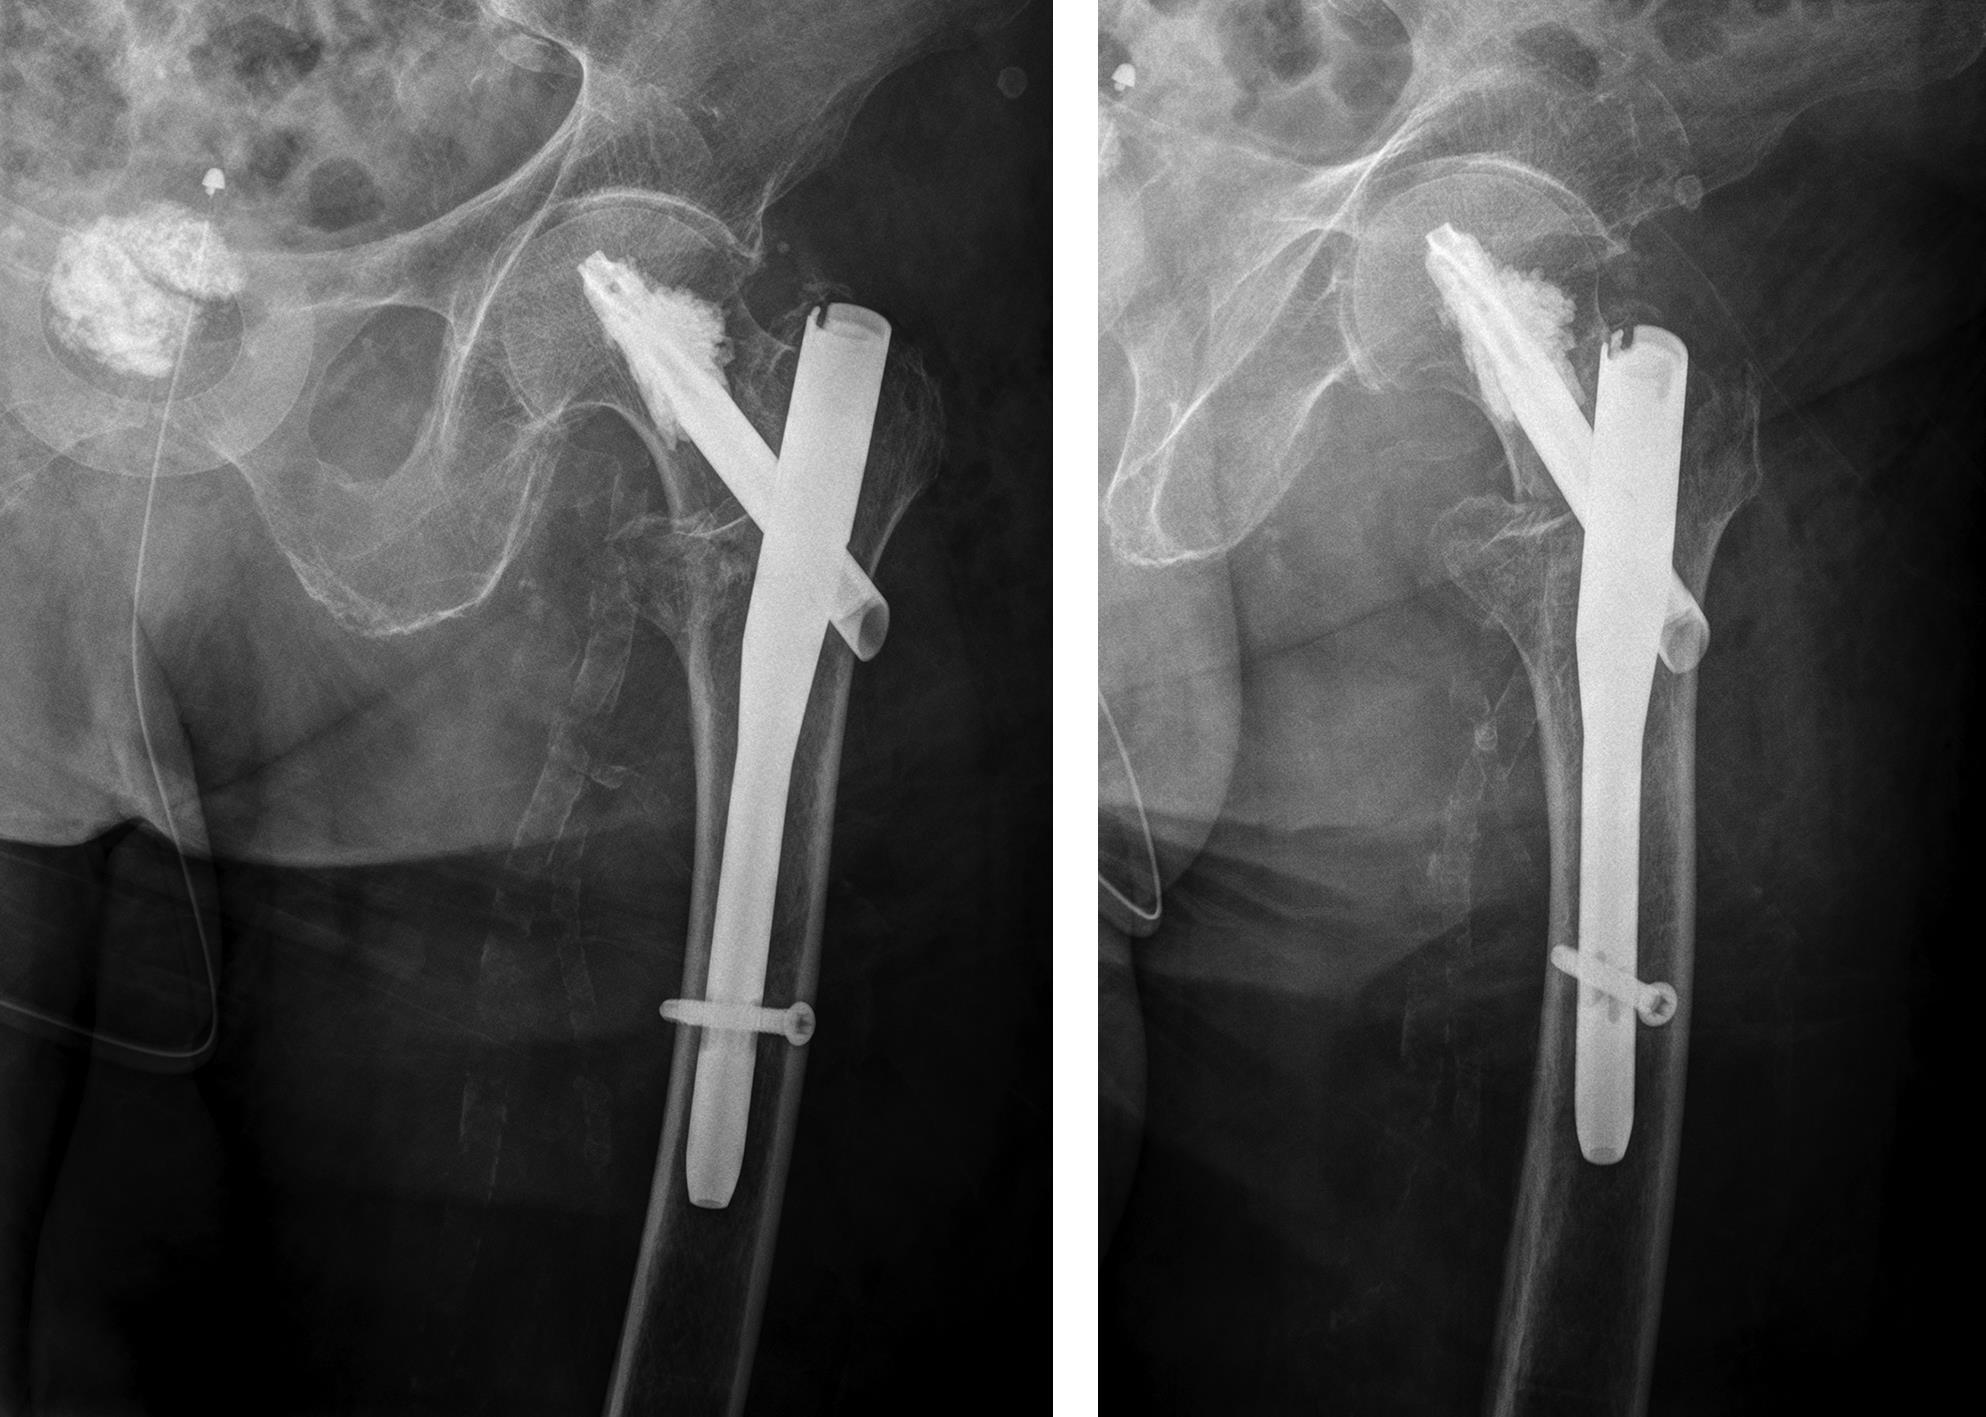

An 83-year-old female patient sustained a 31-A.2.2 fracture of the right proximal femur after a fall at home (Figs 1-2). Intraoperative and postoperative images are shown (Figs 3-5).

A 98-year-old female patient sustained a pertrochanteric fracture of the left proximal femur due to fall in her nursing home (Fig 1). There was significant pain and coxarthritis in the right hip, and hypertension. Surgery was performed within 24 hours. There was an indication for augmentation due to the instability of the fracture. The patient additionally suffered from osteoporosis and dementia.